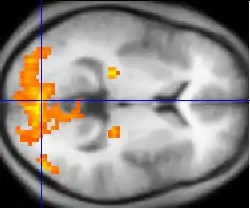

| Functional MRI (fMRI) | Blood-oxygen-level dependent imaging | BOLD | Changes in oxygen saturation-dependent magnetism of hemoglobin reflects tissue activity.[29] | Localizing brain activity from performing an assigned task (e.g. talking, moving fingers) before surgery, also used in research of cognition.[30] | ![]() |

Functional MRI

Functional MRI (fMRI) measures signal changes in the brain that are due to changing neural activity. It is used to understand how different parts of the brain respond to external stimuli or passive activity in a resting state, and has applications in behavioral and cognitive research, and in planning neurosurgery of eloquent brain areas.[48][49] Researchers use statistical methods to construct a 3-D parametric map of the brain indicating the regions of the cortex that demonstrate a significant change in activity in response to the task. Compared to anatomical T1W imaging, the brain is scanned at lower spatial resolution but at a higher temporal resolution (typically once every 2–3 seconds). Increases in neural activity cause changes in the MR signal via T*

2 changes;[50] this mechanism is referred to as the BOLD (blood-oxygen-level dependent) effect. Increased neural activity causes an increased demand for oxygen, and the vascular system actually overcompensates for this, increasing the amount of oxygenated hemoglobin relative to deoxygenated hemoglobin. Because deoxygenated hemoglobin attenuates the MR signal, the vascular response leads to a signal increase that is related to the neural activity. The precise nature of the relationship between neural activity and the BOLD signal is a subject of current research. The BOLD effect also allows for the generation of high resolution 3D maps of the venous vasculature within neural tissue.

While BOLD signal analysis is the most common method employed for neuroscience studies in human subjects, the flexible nature of MR imaging provides means to sensitize the signal to other aspects of the blood supply. Alternative techniques employ arterial spin labeling (ASL) or weighting the MRI signal by cerebral blood flow (CBF) and cerebral blood volume (CBV). The CBV method requires injection of a class of MRI contrast agents that are now in human clinical trials. Because this method has been shown to be far more sensitive than the BOLD technique in preclinical studies, it may potentially expand the role of fMRI in clinical applications. The CBF method provides more quantitative information than the BOLD signal, albeit at a significant loss of detection sensitivity.